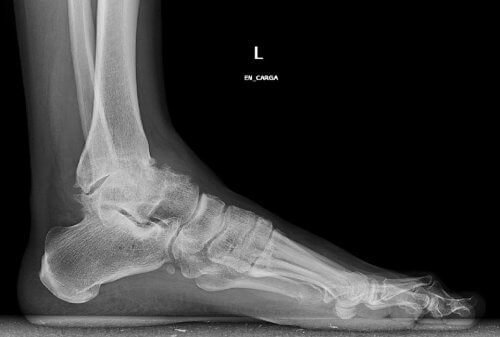

Quando nosso ortopedista dá o diagnóstico, temos a opção de aliviar esse problema mediante uma intervenção cirúrgica conhecida como artroscopia.

- É eficaz nas fases iniciais, onde se corrige a articulação mediante uma operação simples e, na maioria das vezes, rápida.

Por outro lado, e apenas nos casos mais graves, pode-se optar pela prótese do tornozelo onde a destruição da articulação está muito avançada.

Dessa maneira, recuperaremos a total mobilidade da articulação.